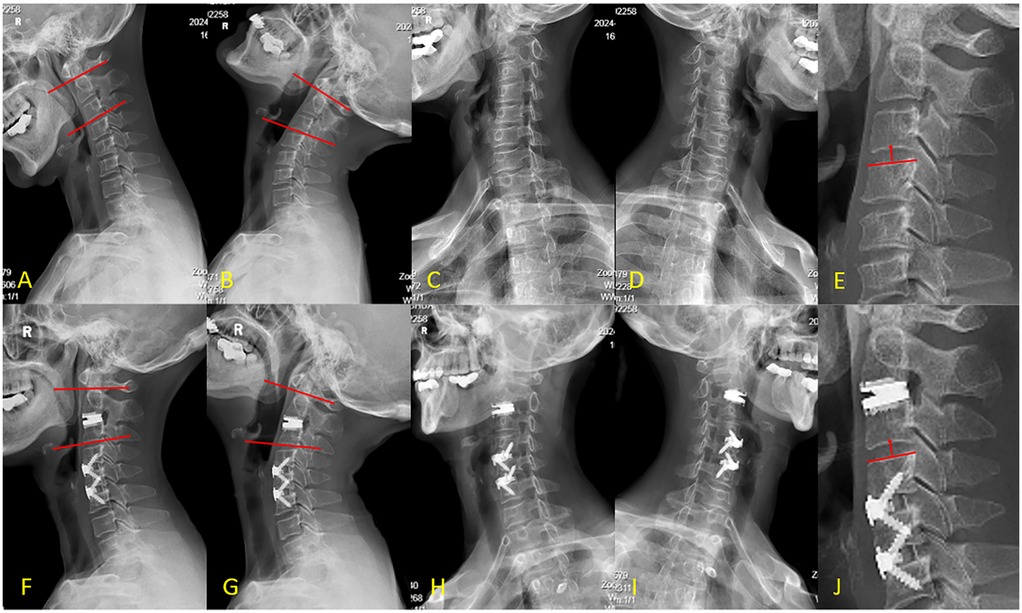

Background Cervical disc herniation at the C2-3 level, resulting in cervical spondylotic myelopathy (CSM), is an uncommon clinical entity. The diagnostic and therapeutic complexity escalates when this pathology coexists with non-contiguous multilevel cervical disc degenerative disease (CDDD). Due to the segmental variability in pathological features, the clinical manifestations of such cases are highly heterogeneous, thereby necessitating a highly individualized treatment strategy. Hybrid surgery (HS), which integrates cervical disc arthroplasty (CDA) and anterior cervical discectomy and fusion (ACDF), offers a tailored approach for the management of multilevel degenerative cervical pathology. The unique anatomical features and surgical technical challenges at the C2-3 level impose significant constraints on treatment options. This article presents a case of non-contiguous three-level hybrid surgery involving CDA at C2-3 and ACDF at C4-5 and C5-6, and discusses the feasibility of this technique for upper cervical disc pathology. Case Presentation A 62-year-old female was admitted with a 6-month history of neck and right upper limb pain, numbness, and gait instability, which had been unresponsive to conservative management. DR revealed loss of the normal cervical lordosis. CT showed no significant osteophyte formation or bony canal stenosis. MRI demonstrated a large disc extrusion at C2-3 causing spinal cord compression, and disc herniations at C4-5 and C5-6 with nerve root impingement. Based on clinical and imaging findings, a diagnosis of multilevel cervical spondylopathy (C2-3, C4-5, and C5-6 disc herniation) was established. The patient underwent anterior cervical discectomy followed by artificial disc arthroplasty (CDA) at C2-3, and anterior cervical discectomy and fusion (ACDF) at C4-5 and C5-6, successfully completing a non-contiguous three-level hybrid surgical procedure. Results Postoperative symptoms were significantly alleviated. At the 12-month follow-up, pain and gait disturbance had largely returned to normal. MRI confirmed adequate decompression of neural compression, DR demonstrated satisfactory range of motion (ROM) at C2-3, and CT revealed satisfactory bone healing at the fused segments. Conclusion CDA serves as an effective alternative for C2-3 disc pathology, achieving neural decompression while preserving segmental mobility. The HS provides a valuable surgical option for the precise treatment of non-contiguous multilevel degenerative disease.